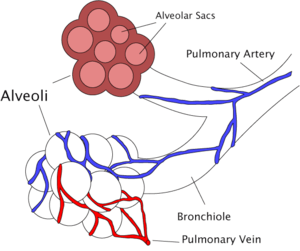

Diagram of the alveoli with both cross-section and external view. | |

The pulmonary veins play an essential role in respiration, by receiving blood that has been oxygenated in the alveoli and returning it to the left atrium.